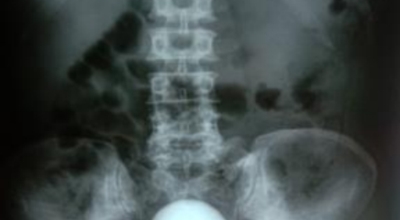

요로결석이란

수분 섭취 감소는 요로결석의 가장 중요한 발병 이유가 되는 것 이라고 합니다. 수분의 섭취가 떨어지면 요석결정이 소변에 머무르는 시간이 길어져 요석형성이 증가하게 되며 요로결석의 발생은 유전적인 소인이 있다는 것이 정설이나 후천적인 생활습관도 관련성을 보입니다.

남성이 여성에 비교해 2-3배 발생 위험성이 높고, 20~40대의 젊은 연령층에서 잘 발생하였지만 최근 고령층에서 발생이 증가하고 있다고 하며 요로결석은 지리적으로 산이 많은 지역, 사막, 열대 지방에서 많이 발생하는데, 이는 음식, 온도, 습도 등이 복합적으로 작용하기 때문이라고 해요. 온도와 계절은 요로결석 발생에 중요한 요인으로 작용하지만, 여름에는 땀을 많이 흘리면서 소변이 농축되어 요로결석의 생성이 용이해진다고 해요.